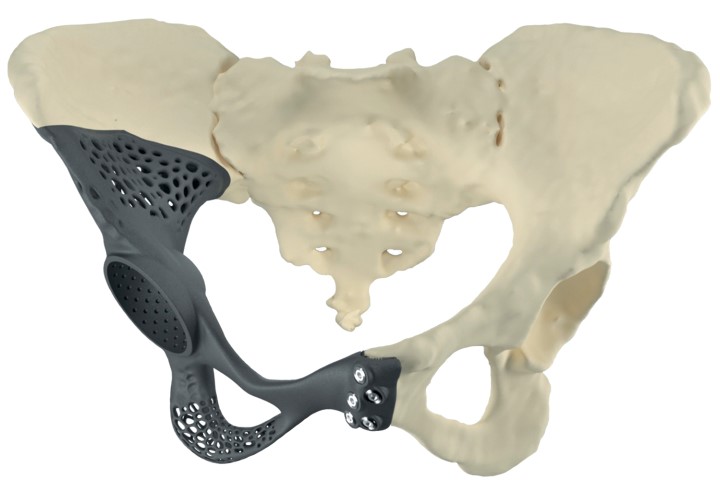

Приклад заміщення дефектів кісток тазу при ураженні пухлиною. Складне індивідуальне ендопротезування кульшового суглоба

ЕТАПИ ПРОЕКТУВАННЯ ІНДИВІДУАЛЬНИХ РЕВІЗІЙНИХ СИСТЕМ

Етапи проектування індивідуальних аугументів для ревізійного ендопротезування колінного суглоба

Етапи проектування імплантатів при онкопротезуванні

Етапи онкологічного протезування